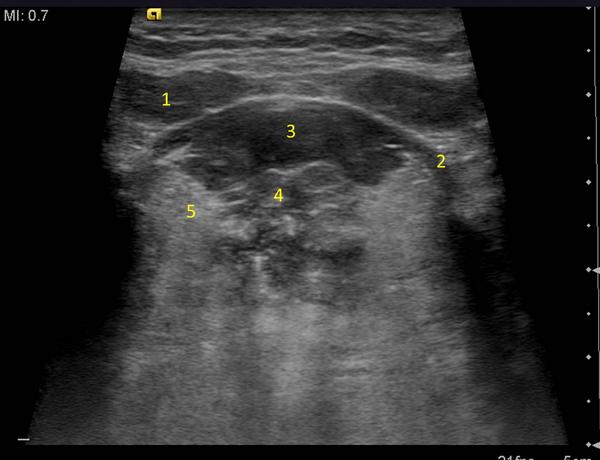

Ultrasound Neck Anatomy

Ultrasound neck anatomy. While the vast majority of patients are supine on the exam table with a pillow supporting the shoulders to allow gentle neck extension keep in mind that some patients have beautiful anatomy d that allows ultrasound exam even in a sitting position. The visceral space contains the thyroid parathyroid glands larynx hypopharynx the cervical trachea and esophagus the recurrent laryngeal nerve. This can be confirmed from ultrasound guided fnac allowing appropriate clinical management and treatment.

A common neck ultrasound is ultrasound of the thyroid which uses sound waves to produce pictures of the thyroid gland within the neck. These include the masseter muscle the zygomatic arch and the outer cortex of the ramus of the mandible and the suprazygomatic portion of the temporalis muscle. It does not use ionizing radiation.

A neck ultrasound is performed to diagnose potential problems of the thyroid lymph nodes and carotid arteries. In the infrahyoid neck it is surrounded by the anterior cervical space anteriorly by the visceral and retropharyngeal spaces medially and by the perivertebral and posterior cervical spaces posteriorly. Anterior neck anatomy false vocal cords true vocal cords paraglottic fat.